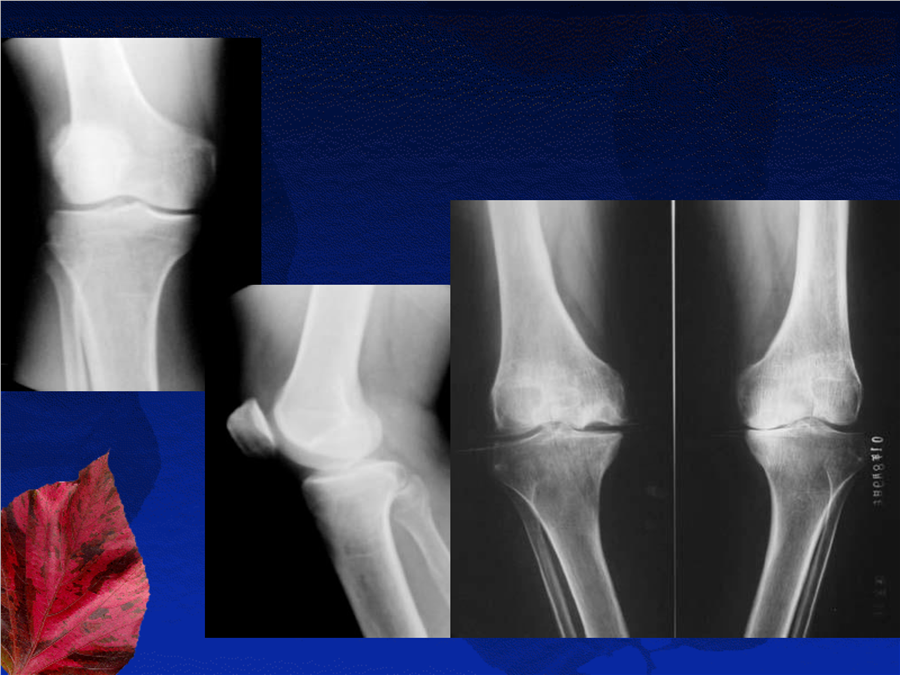

骨关节系统